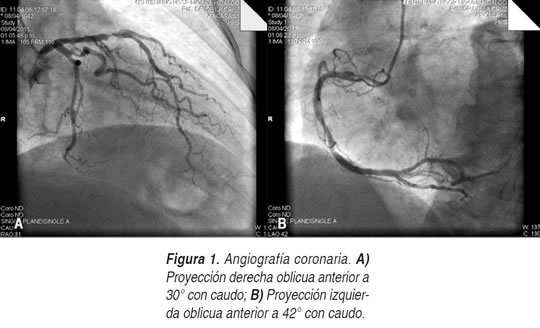

Se presenta el caso de una mujer de 70 años de edad, que acudió al Servicio de Urgencias con un cuadro de siete días de evolución caracterizado por desorientación, miopatía y anuria. Como antecedentes de importancia: tabaquismo crónico a razón de 5 cigarros/día (índice tabáquico 12.5 paquetes/año), exposición crónica a humo de leña, historia de hipertensión arterial y diabetes mellitus diagnosticados hace 10 años; un mes previo presentó clínica (angor pectoris típico), electrocardiográfica (elevación transitoria del segmento ST e isquemia subepicárdica anterolateral) y bioquímica (troponina positivo) de un infarto agudo del miocardio anteroseptal, cateterismo cardiaco izquierdo, concluyendo lesión proximal de la descendente anterior del 95%, lesión proximal de la circunfleja de 60% y lesión en 1er. ramo obtuso marginal de 70% y dos lesiones en el segmento vertical de la coronaria derecha de 30 y 40% (Figura 1). Se determinó la necesidad de revascularización quirúrgica con función renal y hepáticas adecuadas a 96 h del cateterismo y con tratamiento médico óptimo vía oral: Aspirina 100 mg/día, clopidogrel 75 mg/día, enalapril 5 mg cada 12 h, metoprolol 25 mg cada 12 h, simvastatina 80 mg/día y mononitrato de isosorbide 50 mg/día; fue programada para cirugía de revascularización coronaria.